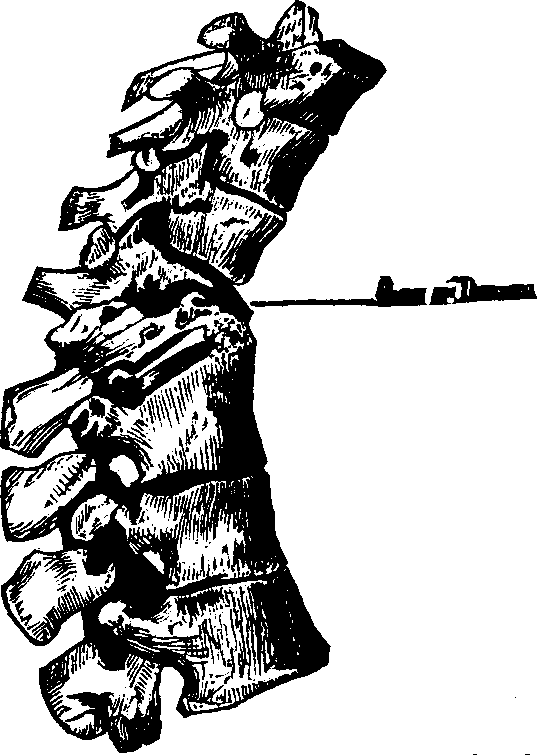

Fig. 14. Backbone, spinal

column, or vertebral column. All animals possessing such a row of bones are

called vertebrates. Above b are the cervical (neck)

vertebræ; b to c, dorsal (back) or chest

vertebræ; c to d, lumbar (loins) vertebræ;

d to e, sacrum; e to f, coccyx.

The Spinal Column or backbone, when viewed from the front presents a perpendicular appearance, but a side view shows four distinct curves. The bones composing it are called vertebræ. The body part of a vertebra is light and spongy in texture, having seven projections called processes, four of which are the articular processes, which furnish surfaces to join the different vertebræ of the spinal column. Two are called transverse, and the remaining one is termed the spinous. The transverse [pg 25]and spinous processes serve for the attachment of the muscles belonging to the back. All these processes are more compact than the body of the vertebra, and, when naturally connected, are so arranged as to form a tube which contains the medulla spinalis, or spinal cord. Between the vertebræ is a highly-elastic, cartilaginous and cushion-like substance, which freely admits of motion, and allows the spine to bend as occasion requires. The natural curvatures of the spinal column diminish the shock produced by falling, running or leaping, which would otherwise be more directly transmitted to the brain. The ribs at the sides, the sternum in front, and the twelve dorsal bones of the spinal column behind, bound the thoracic cavity, which contains the lungs, heart, and large blood-vessels.